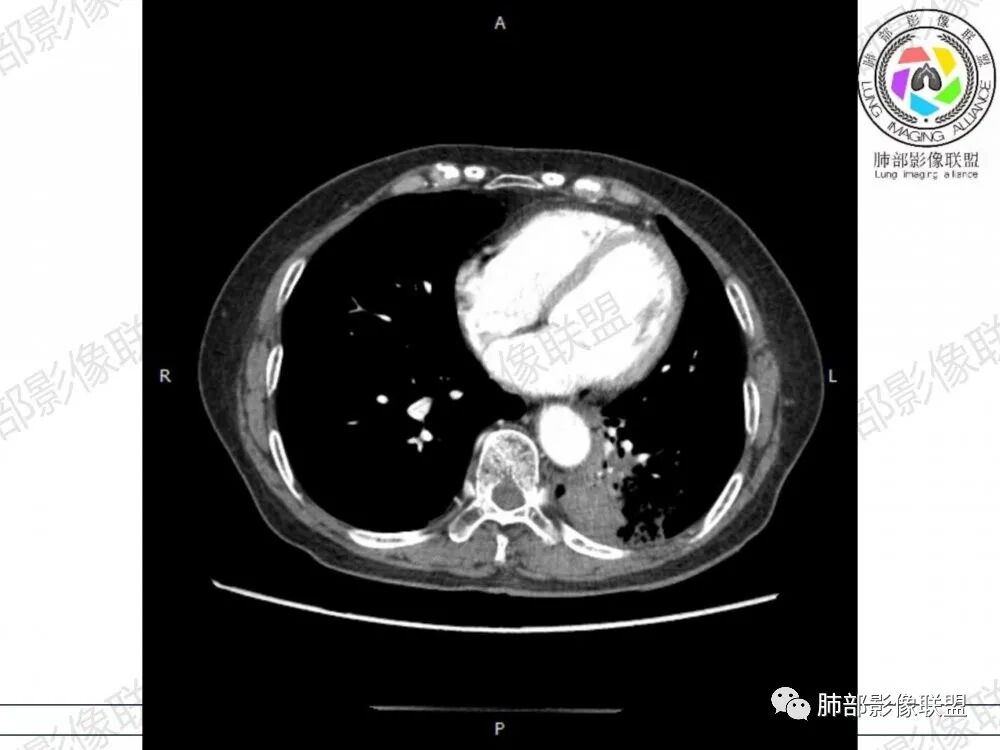

晨读病例,老年人男性 左肺下叶病灶,实性病变加上边界清晰的磨玻璃影,实性病变可见明显的膨胀性生长,增强实性部分可见血管照影征,考虑腺癌,粘液腺癌可能。

左肺下叶胸膜下混合磨玻璃影,磨玻璃边界清晰,支气管进入后堵塞,增强轻中度强化,无明显坏死空洞。

空腔+铺路石征+边界清楚GGO+病灶内血管局部扭曲+强化不均匀+病史长,指向腺癌,特别是粘液腺癌

晨读:左肺下叶胸膜下实性高密度影,部分伴有网格样增厚,内部可见小空泡,壁光滑,周围伴有磨玻璃影,边界清,近端可见支气管穿行,远端支气管堵塞,胸膜下脂肪间隙可见,病变整体收缩,部分有彭隆,增强后可见血管穿行,强化尚均匀。

左肺下叶实变及磨玻璃影,宽基底与胸膜相远,磨玻璃边界清晰,边缘膨隆,病变内近端支气管堵塞,不均匀强化,可见血管影,考虑腺癌,鉴别结核

胸CT:左下叶胸膜下大片斑片影,长轴沿胸膜分布,实变、GGO混杂,磨玻璃边界清晰,粘液密度,小叶内间隔增厚,支气管进入后堵塞(枯枝),增强轻中度强化,血管造影征。常规考虑:肺腺癌?淋巴瘤?鉴别不典型病原体感染。

周围GGO,呈碎石路征,边界清楚

主体病灶

应该是空洞

2、影像表现:无肺气肿背景,病变定位于左肺下叶背内侧基底段,病灶呈不规则团块影,靠近胸膜侧,其内密度不均匀,内见空洞、实变及磨玻璃影,磨玻璃影呈碎石路征,边界清楚,实性肿块边界膨隆,其内见空洞。空洞周围比较实。病灶较大的支气管通畅,细小的支气管成“枯枝征”。无胸膜增厚及胸膜腔积液,增强扫描呈中度强化,见血管造影征。